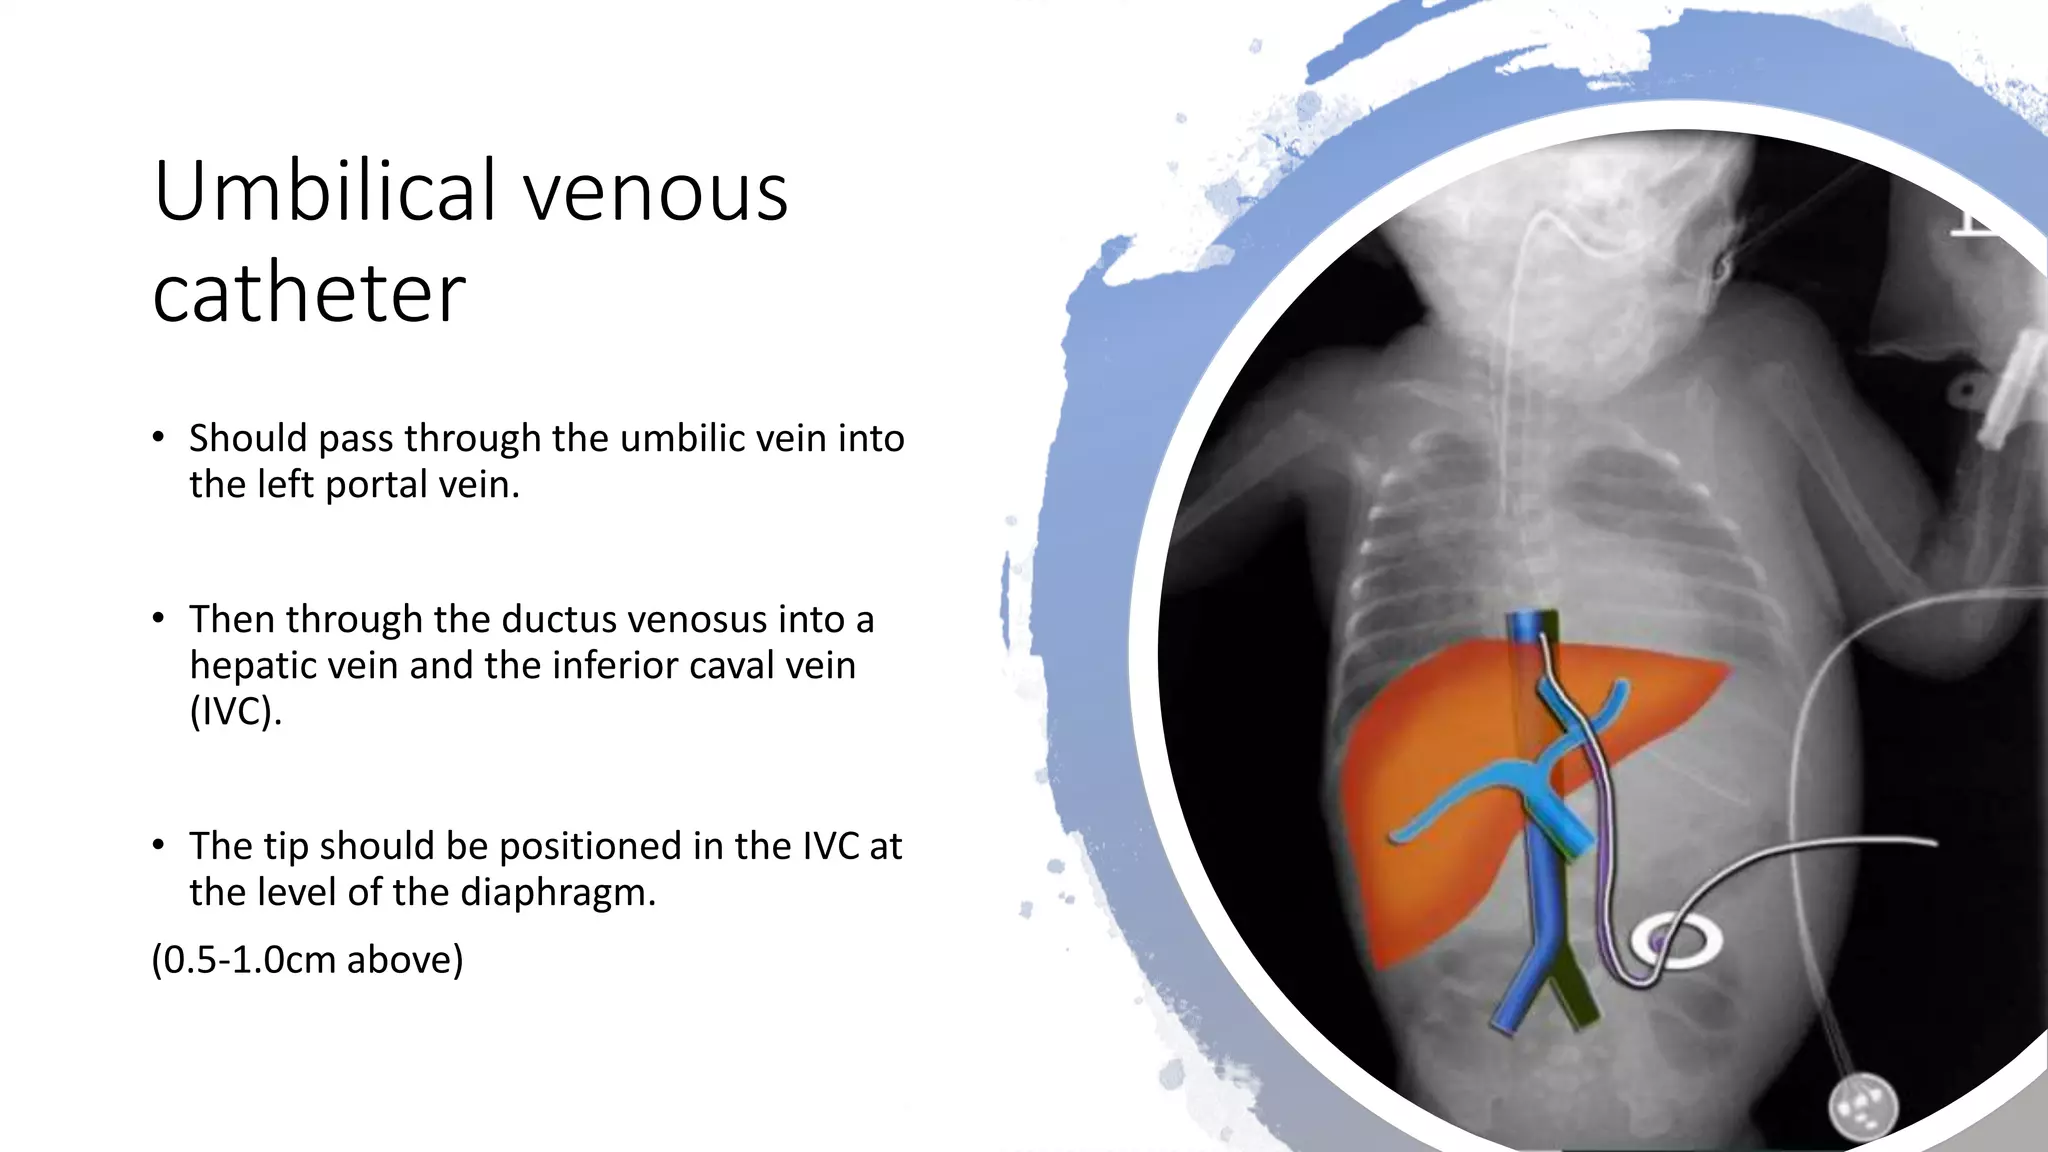

This document provides an overview of neonatal chest x-rays, including when they should and should not be performed, what a normal x-ray looks like, common positions of tubes and catheters, and common causes of respiratory distress in neonates. It discusses the appearance of a normal chest x-ray as well as conditions like respiratory distress syndrome, transient tachypnea of the newborn, meconium aspiration syndrome, and pneumonia. Surgical conditions like diaphragmatic hernia and esophageal atresia are also reviewed.